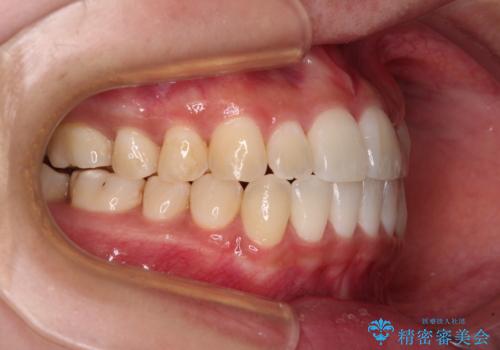

すきっ歯とオープンバイトをインビザラインで改善

- 前歯の上下スペースと前歯の隙間を気にして来院された患者様です。

インビザラインにより上下の前歯の隙間を閉じていくこととしました。

上下の隙間に舌が入り込むことが、すきっ歯やオープンバイトの原因であったため、舌の筋肉のトレーニングも並行して行い、後戻りの抑制を図りました。